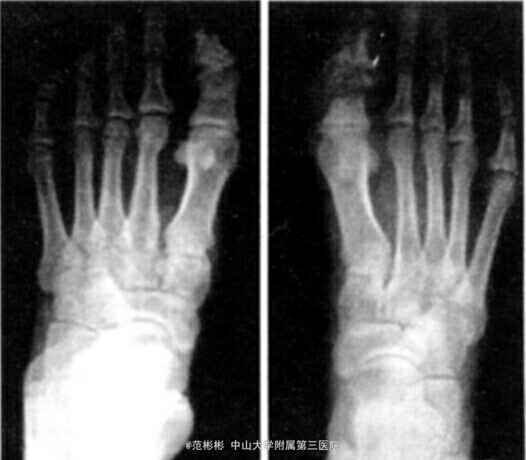

入院检查 :神智清楚,智力正常,头颅外观正常,身高 170 cm,牙齿排列整齐、无脱落。右趾、左第 1~4 足趾、双手手指末梢呈淡粉红色,变形、无压痛。右 趾趾甲畸形,皮肤质硬、皲裂。类风湿因子 (-),抗“ O”试验(-),梅毒抗体 (-),肝、肾功能无异常, 右 指分泌物细菌培养 (-),红细胞沉降率正常,甲状旁腺激素正常。 X 线片检查示:中指,左示、中、无名指末节指骨骨干明显变细、基底部完整 ;右趾远节骨质溶解伴缺失,近节趾骨和趾间关节破坏 ;左 趾、小趾末节部分骨质溶解;全身其余骨质未见异常。